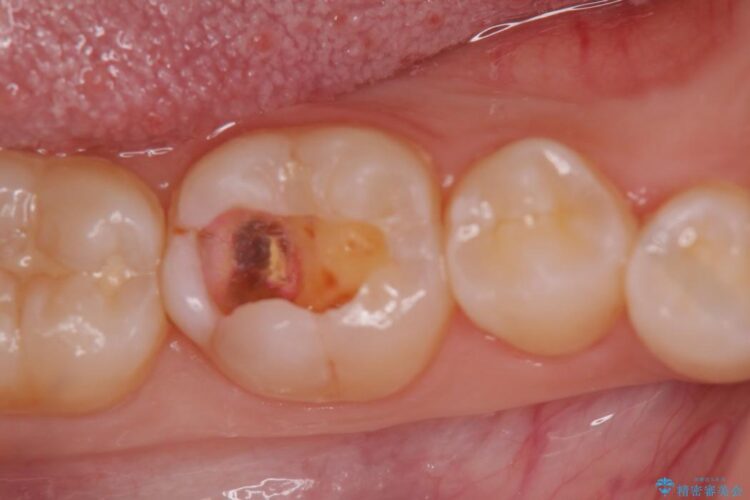

黒ずんでいる歯が気になりご来院されました。

診査をした結果、顎左右の前から6番目の歯に深い虫歯があったため、詰め物(インレー)タイプで修復していく(e-max プレスインレー)での治療を行いました。

今回は歯の黒ずみを気にしてご来院されましたが、診査をしますと神経の治療が必要になる一歩手前の状態である神経の近くまで虫歯が広がっていました。

早めの治療を行えたことにより詰め物での治療にて治すことができました。